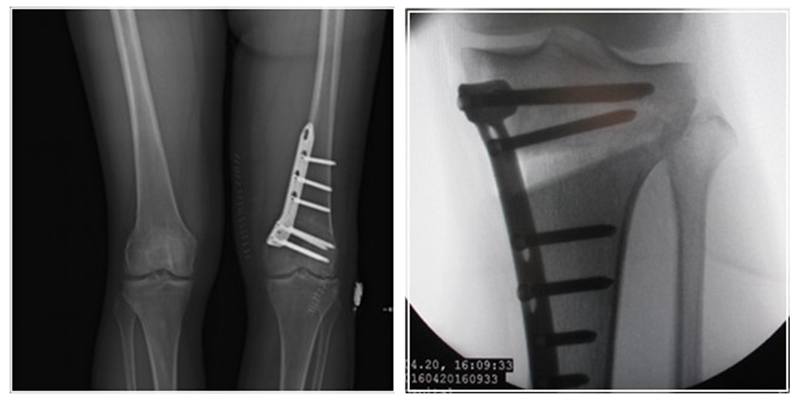

术后影像

患者二,女性,膝外翻,膝外侧疼痛。通过做畸形分析后发现,该患者同时存在股骨侧畸形、胫骨侧畸形和关节内畸形(LDFA=82°,MPTA=104°,JLCA=6°)。

对于这类病人如何进行术前设计的关键点就在于目标力线应如何设计。要在骨性截骨的时候纠正骨性畸形,关节内畸形要通过关节内的方法解决。因为JLCA不平行,所以要同时画股骨侧关节线和胫骨侧关节线,并垂直于股骨侧关节线做出股骨侧目标力线,垂直于胫骨侧关节线做出胫骨侧目标力线。

根据各自目标力线,分别计算股骨内侧闭合和胫骨内侧闭合角度。

此患者股骨内侧闭合6°,经股内侧闭合13°。